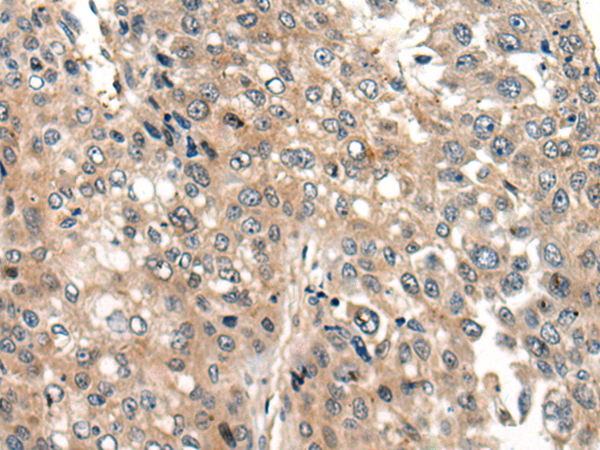

分类: 科研抗体货号: P06266别名: NCBP; Sto1; CBP80应用: WB,IHC反应种属: Human, Mouse, Rat